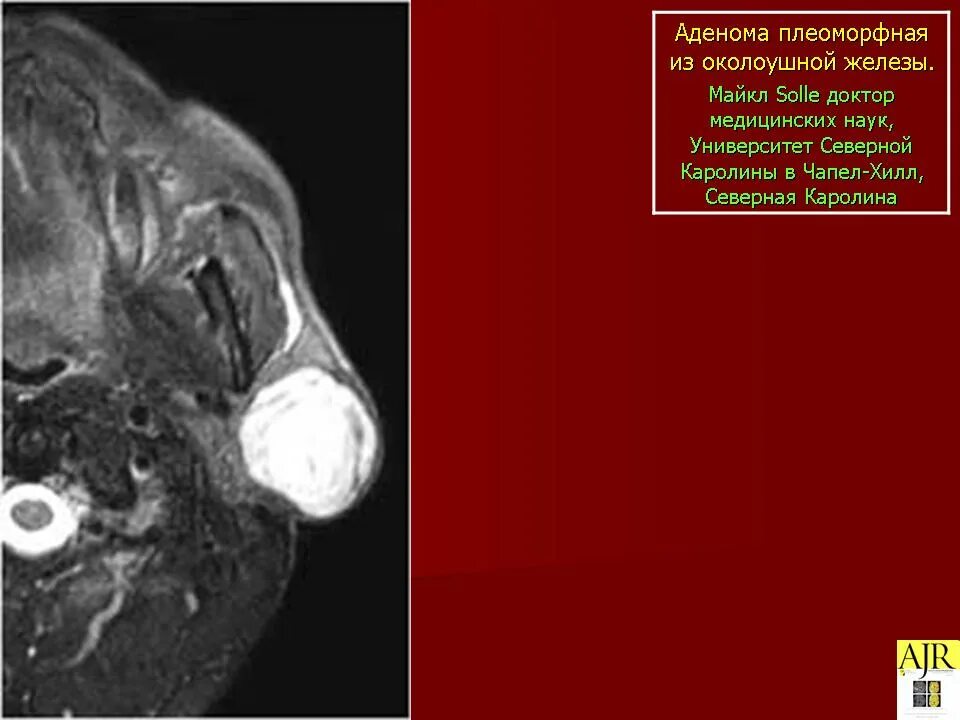

Ли аденома